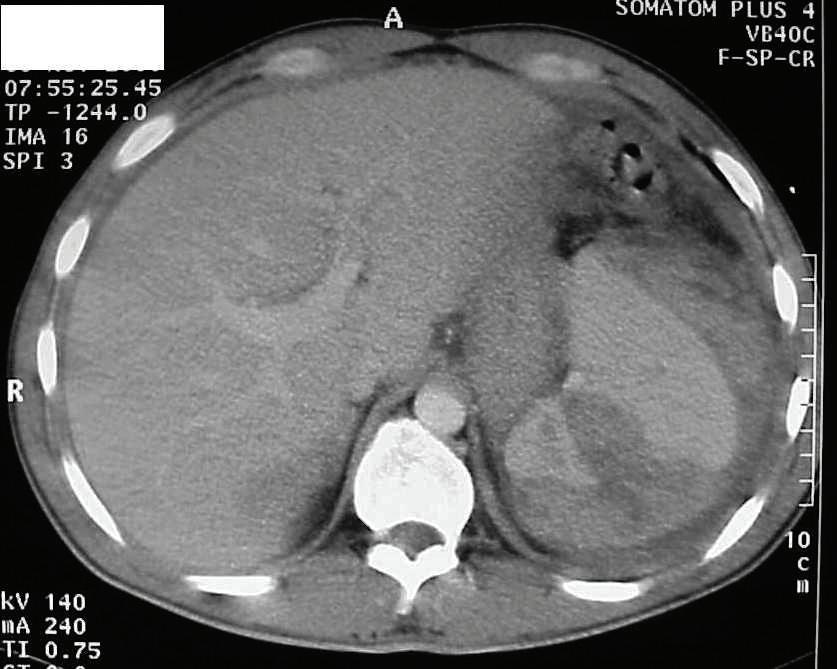

20-годишна бременна жена в 29 ге -

стационна седмица, примигравида, е хоспитализирана в Клиниката

по акушерство и гинекология на УМ -

БАЛ ,,Д-р Георги Странски” – гр. Пле -

вен с преждевременно пукнат око -

лоплоден мехур, високи стойности на артериалното налягане (150/100 mmHg) и изразени отоци по долните крайници. Пациентката е с придружаващо заболяване ЗДТ1, диагностициран в детска възраст, на терапия с бързодействащ инсулинов аналог (Glulisine) и дългодействащ инсули -

нов аналог (Glargine). Анамнестичните данни показват, че пациентката е с

повишено артериално налягане от 20 дни със стойности до 160/100 mmHg,

кифосколиоза, силно раздути дебелочревни бримки, ехопозитивни тънкочревни бримки, единична пъпна артерия, десностранно криво ходило, съмнение за артрогрипоза на големите стави, отговарящи на caudal regression sequence.

Физикалният преглед на бременната показа нормална белодробна функция с везикуларно дишане без добавени хрипова находка и норморитмична, нормофреквентна сърдечна дейност с АН 150/100 mmHg.

околоплодна течност, което затруднява визуализацията на вътрешните органи на плода. Прави впечатление

на същите. Проведе се токолитична терапия, антибиотична

провежданата антихипертензивна терапия.

На третия ден от хоспитализацията мултидисциплинарен екип обсъди по-нататъшното поведение. Взе се решение за родоразрешение чрез Цезарово сечение в интерес на майката поради екстремно незрелия гестационен срок, седалищно пред

персистиращите високи стойности на артериалното налягане и

от УЗИ за малформативен плод.